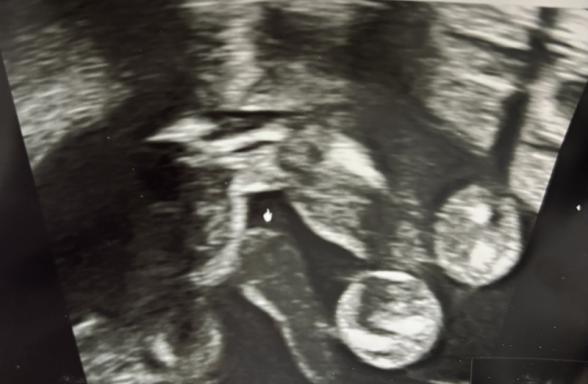

妊娠19週でスクリーニング検査をしてもらったのですが、性別は女の子かもしれないけど不確定と言われました。

確かに股は平らなのですが、割れ目は見えないので男の子の可能性もある、、?

写真を見て判断していただけると嬉しいです。

せっかくご質問いただきましたが、こちらのエコーの写真だけで、性別をお答えするのは難しいです。

まだ基本的には、間違いがあってもよくないので、性別に関する回答は控えさせていただいております。